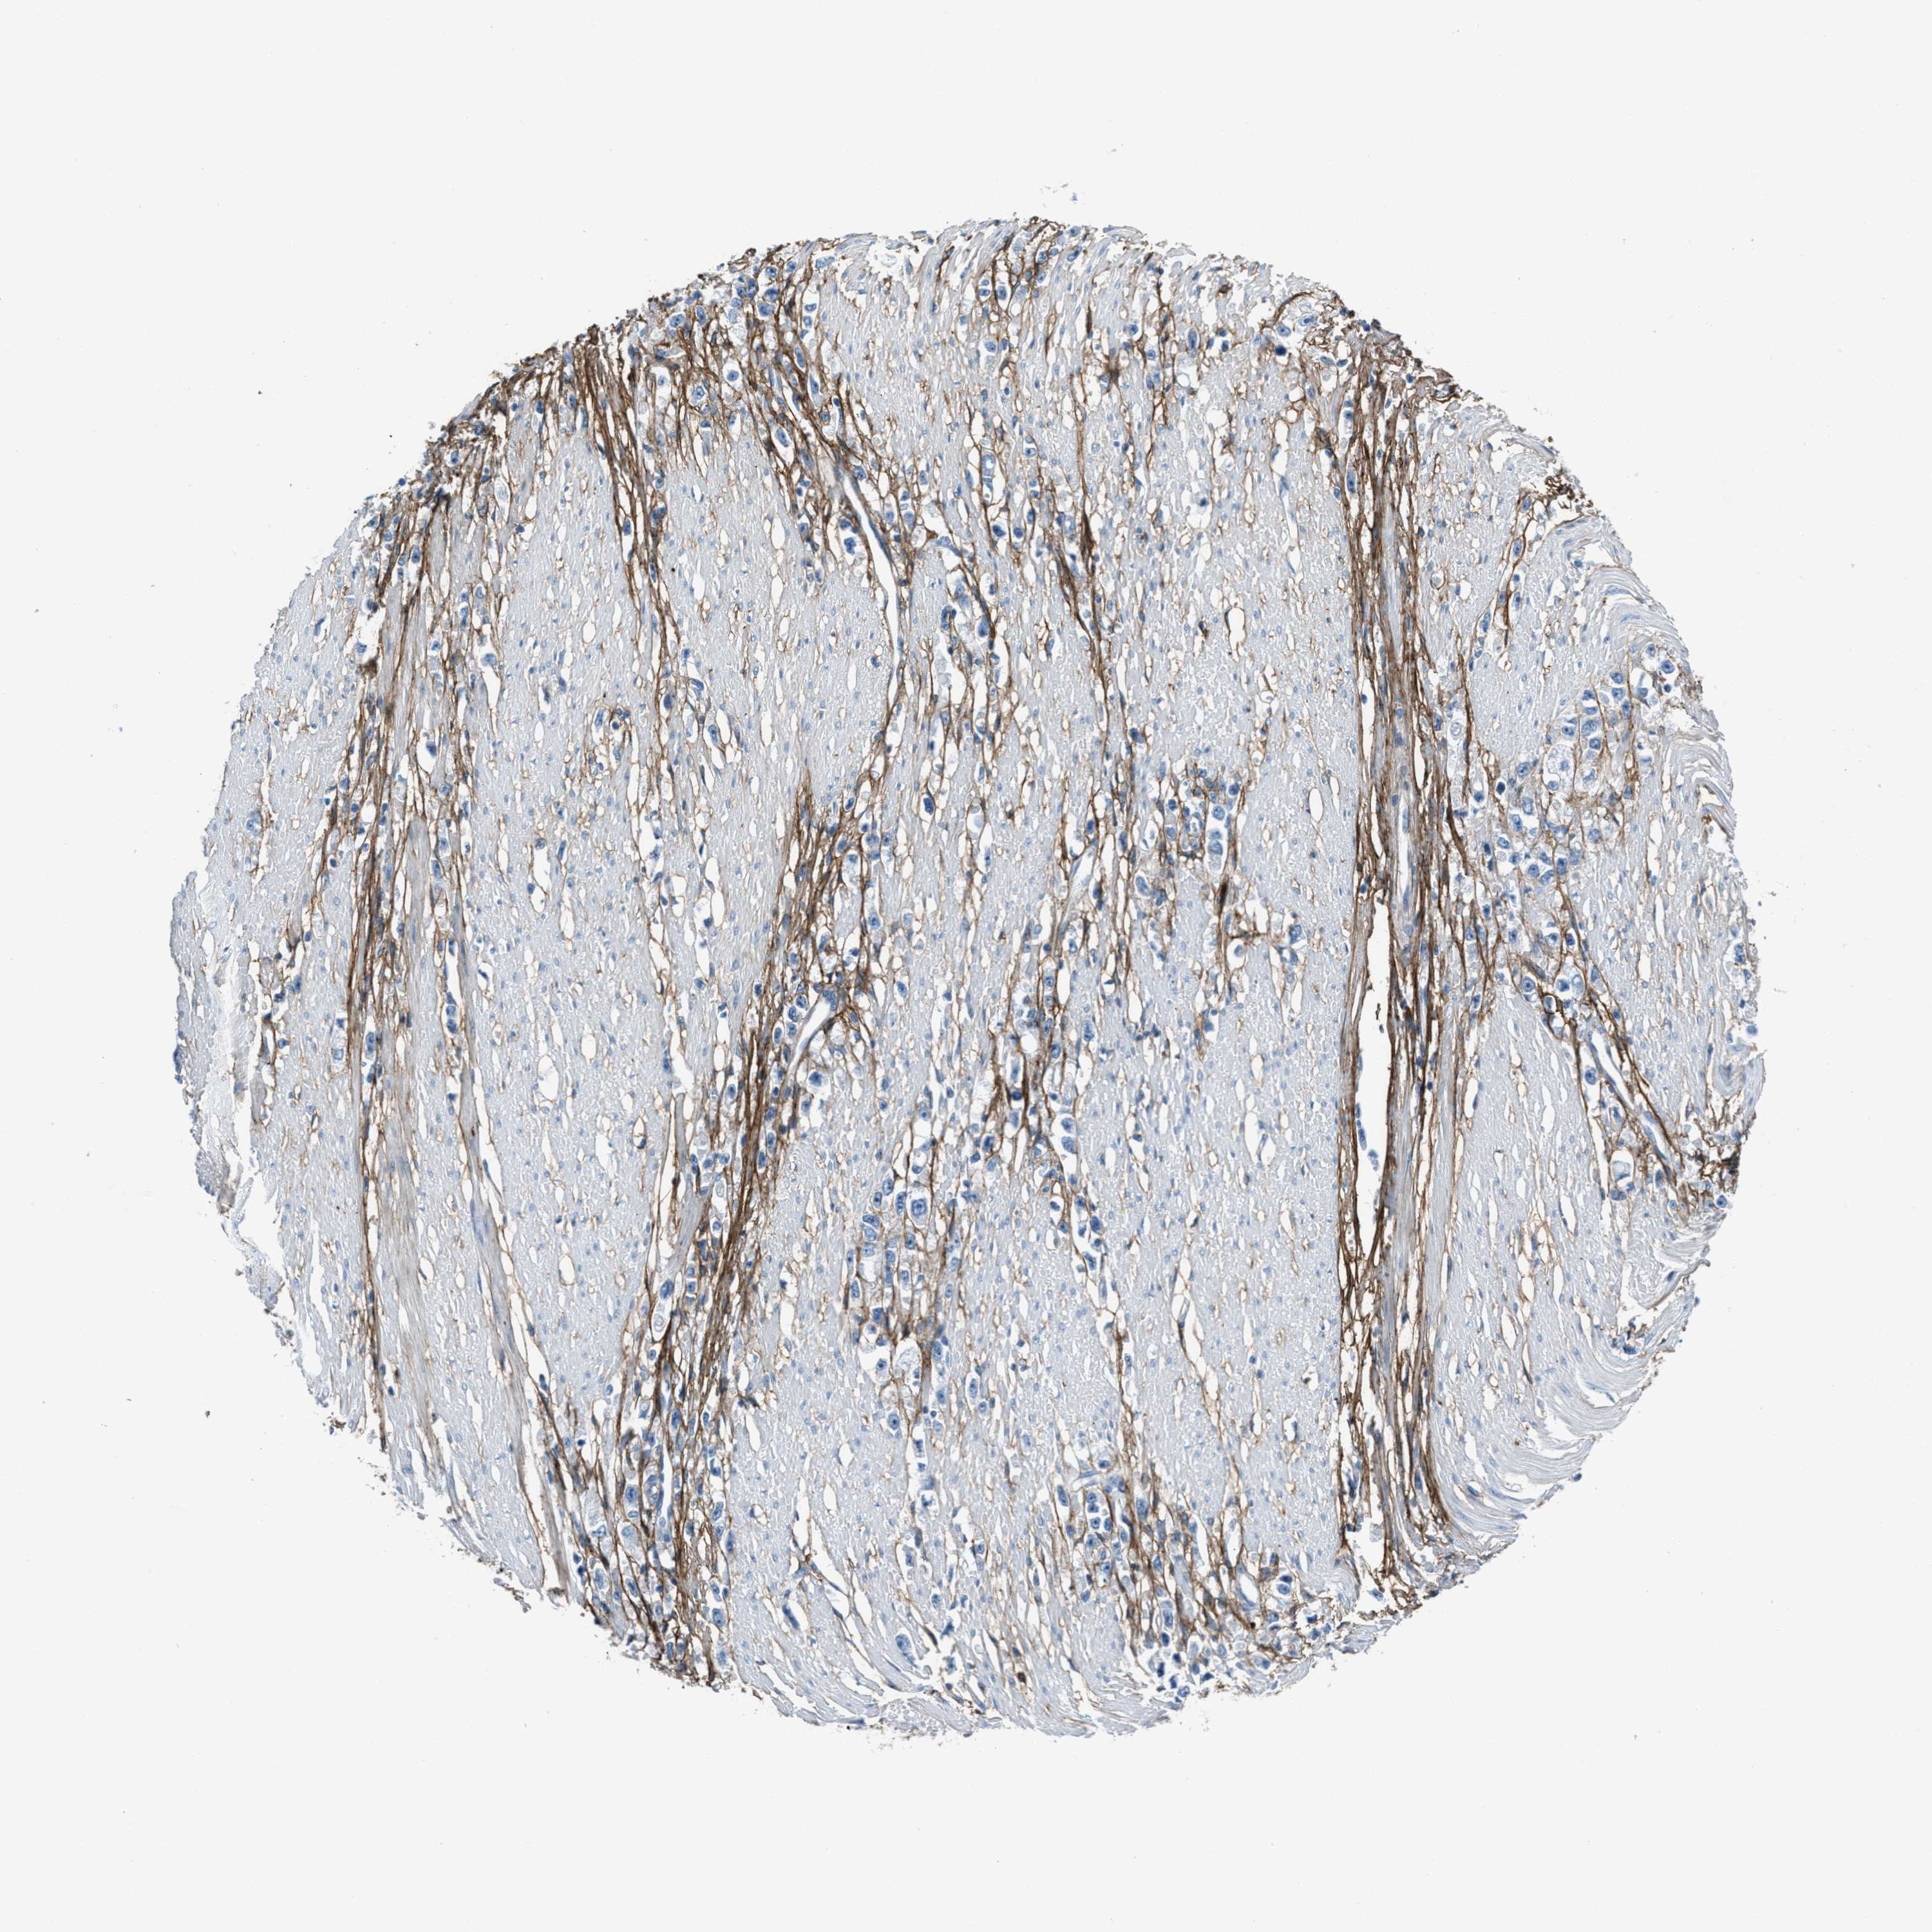

STOMACH CANCER - Protein expressioni

A mouse-over function shows sample information and annotation data. Click on an image to view it in a full screen mode. Samples can be filtered based on level of antibody staining by selecting one or several of the following categories: high, medium, low and not detected. The assay and annotation is described here.

Note that samples used for immunohistochemistry by the Human Protein Atlas do not correspond to samples in the TCGA dataset.

Antibody stainingi

Antibody staining in the annotated cell types in the current human tissue is reported as not detected, low, medium, or high, based on conventional immunohistochemistry profiling in selected tissues. This score is based on the combination of the staining intensity and fraction of stained cells.

Each image is clickable and will lead to virtual microscopy that enables deeper exploration of all samples and also displays staining intensity scores, fraction scores and subcellular localization as well as patient and tissue information for each sample.

HPA017759

HPA021057

CAB002670

CAB058696

CAB068188

CAB080202

Staining

High

Medium

Low

Not detected

Intensity

Strong

Moderate

Weak

Negative

Quantity

>75%

75%-25%

<25%

None

Location

Nuclear

Cytoplasmic/membranous

Cytoplasmic/membranous,nuclear

Adenocarcinoma, NOS

Adenocarcinoma, High grade